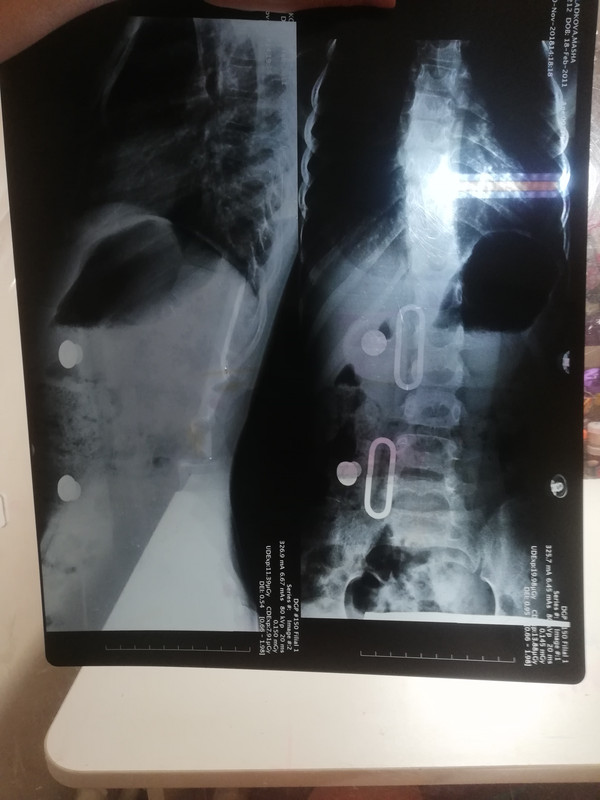

Да, наш отчёт за месяц, что мы в корсете:

Динамика

Это наша маленькая победа

На снимке слева-июнь 2018,справа-свежий снимок. После июня было сильное ухудшение, сильный перекос, вырос большой горб, снимка у нас не было. В корсете с конца октября 20/24,без пелотов.

Последний месяц мы на системном спорте, 3раза/неделю бассейн и 1раз занятие с реабилитологом.

Ну наконец то у вас все наладилось, ребенок счастлив, мама тоже ))) Что касается снимка, положительная динамика есть,но не большая, имхо. Наверно стоит усилить давление, вклеить пелоты.

natik2012 так и планировалось. Месяц привыкание к наличию корсета, и после коррекция и пелоты. На этой неделе должны ставить. Страшно, конечно, мучить ребенка=(

Тут главное, что эта динамика, пусть и не большая, послужила лучом света, когда понимаешь, что выход есть! А не крест, как говорили нам ранее..